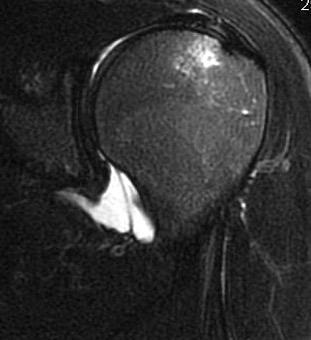

Capsular tears

Clinical

Anterior instability

Intact labrum on MRI

Anterior labrum intact, evidence of capsule tearing + HAGL on MRI